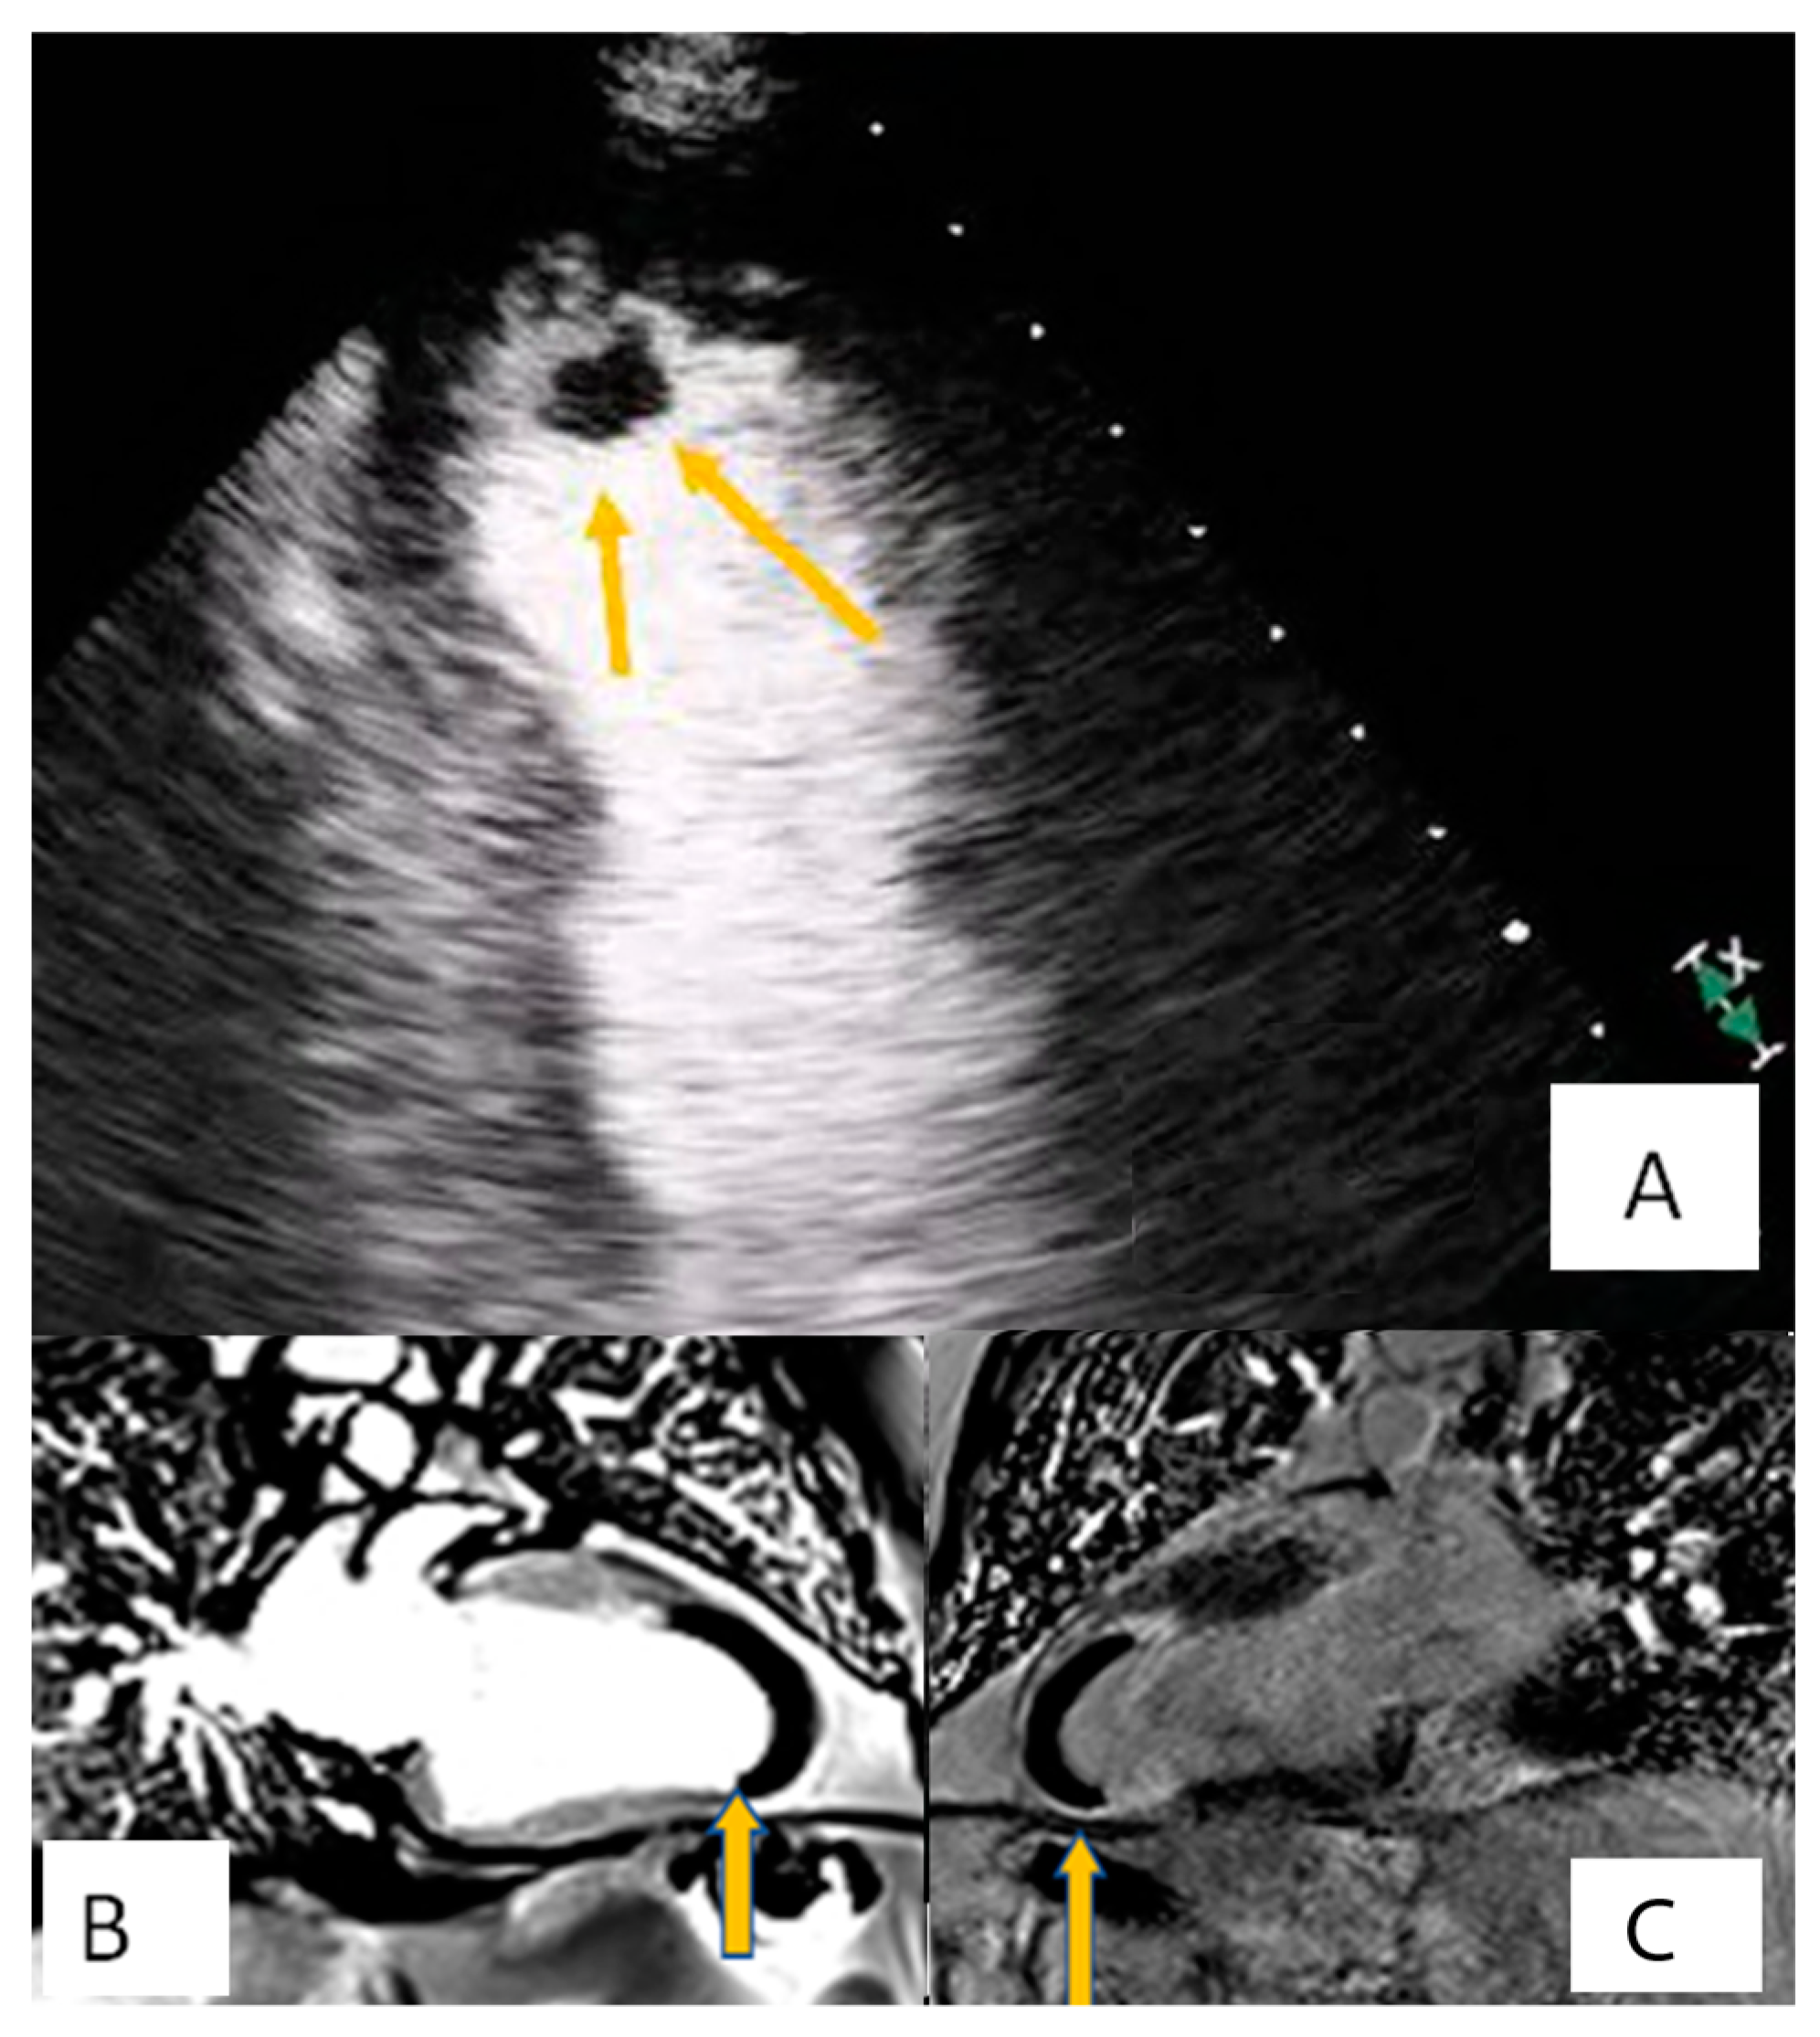

3.1. Transthoracic Echocardiography

3.2. Transesophageal Echocardiography